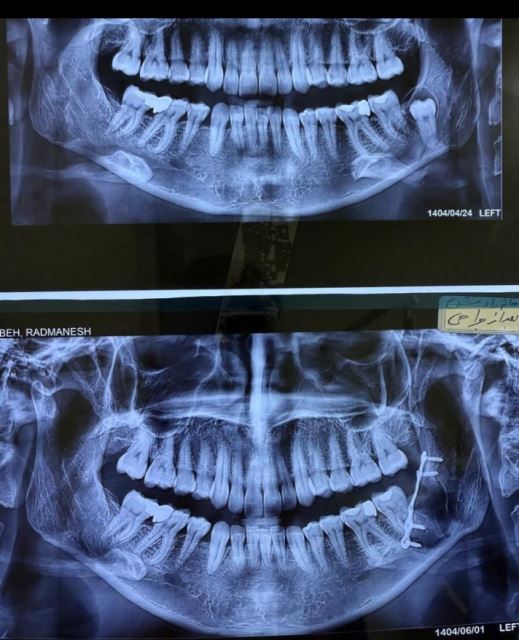

جراحی دندان عقل نهفته

دندان نهفته کیست و‌ احتمال شکستگی فک